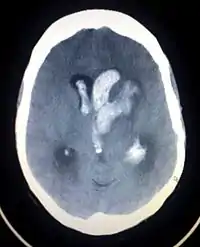

| سیتی اسکن قسمتی از مغز که ایسکمیک ناشی از سکته مغزی را نشان میدهد. | |

درمان اولیه پس از وقوع یک سکته مغزی شامل تحت نظر گرفتن دقیق فرد و انجام اقدامات پرستاری برای محافظت راه تنفسی او میباشد. اگر در سی تی اسکن دیده شد که یک لخته خون در شریان وجود دارد، باید فوراً با استفاده از داروهای ترومبولیتیک اقدام به حل کردن آن نمود. این درمان ممکن است باعث بهبود عواقب سکته مغزی بشود اما در هر موردی نباید آن را بکار برد، زیرا باعث افزایش خطر بروز خونریزی در مغز میشود.